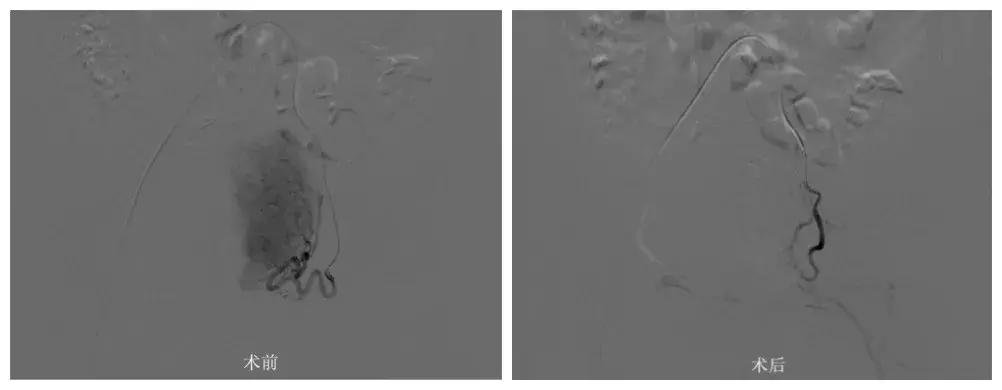

省二医介入科主任肖承江介绍,静静因患子宫腺肌症,子宫内膜长进了子宫的肌肉里,每次月经期异位内膜出血无法排出,导致子宫收缩,疼痛感剧烈。“除了切除子宫,介入治疗是有效缓解疼痛的方法,所以根据患者病情及生育情况,我们采用了经股动脉穿刺栓塞腺肌症供血血管治疗。”手术很顺利,术后三个月,静静正常月经期两次都没有任何疼痛感。